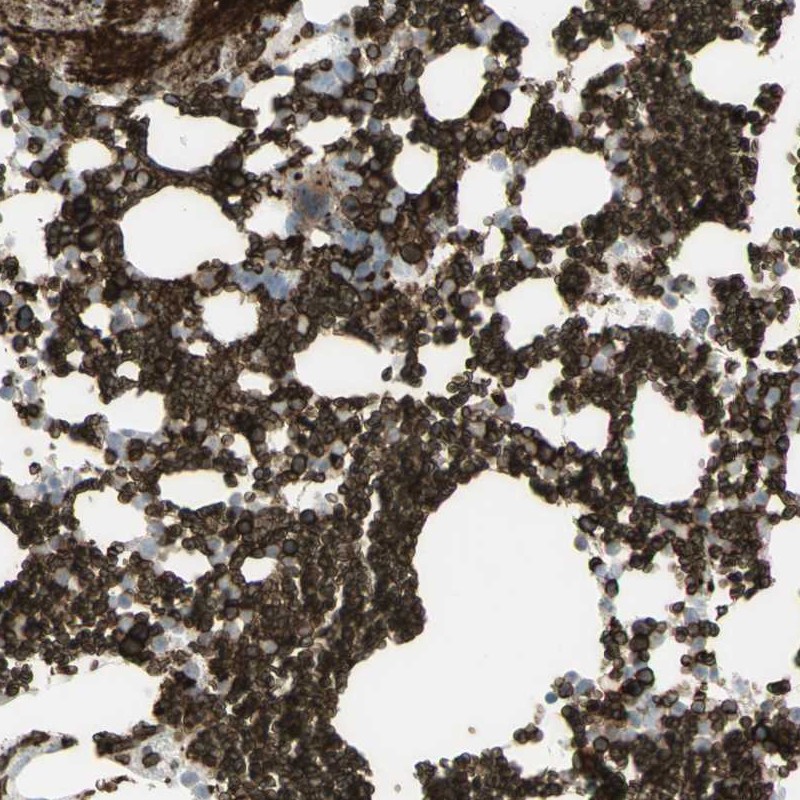

Immunohistochemical staining of human bone marrow shows strong positivity in erythrocytes and subsets of hematopoietic cells.